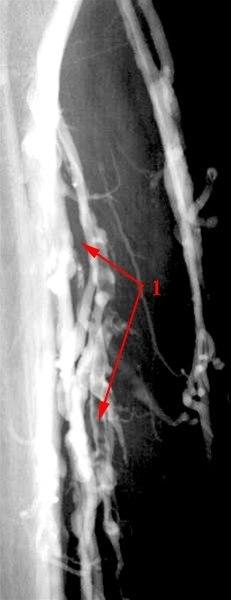

Trombe i en av leggens dype vener (1)

Tromben framstår som oppklaring sentralt i venen med kontrast langs veggen